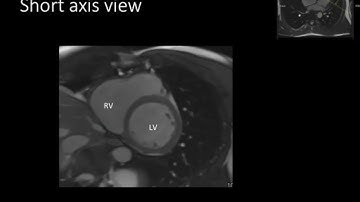

MRI – CARDIAC IMAGING : KEY PARAMETERS OF CINE TRUEFISP EXPLAINED